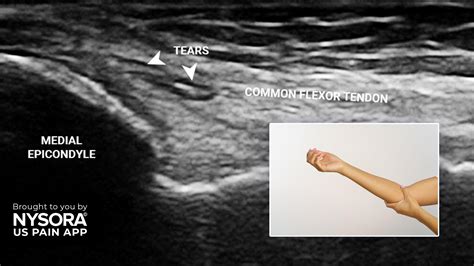

To manage this condition, you first need to understand why it happens. Golfer's elbow is primarily an overuse injury. In golf, the force generated during the downswing, especially if you catch the turf behind the ball or have an improper grip, places significant torque on the elbow tendons. If the muscles in your forearm are weak or tight, the tendons take the brunt of that impact, leading to micro-tears and chronic inflammation.